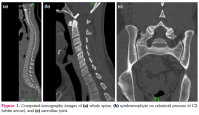

A 22-year-old male patient was admitted to the rheumatology clinic due to neck and back pain with morning stiffness for 12 months. He suffered from right knee and heel pain six months ago. He showed increased levels of high-sensitivity C-reactive protein (2.20 mg/dL, reference range: 0.01-0.3 mg/dL) and erythrocyte sedimentation rate (67 mm/h, reference range: 0-15 mm/h). To evaluate neck and back pain, the physician performed computed tomography (CT) of the whole spine. The CT finding was absence for herniated nucleus pulposus nor neural foramen stenosis. All vertebral corners of whole spine were clear (Figure 1a), except for bony spur at odontoid process of C2 (Figure 1b, white arrow).

Upon suspicious of ankylosing spondylitis (AS), CT scan for sacroiliac joints and sacroiliac joint, and human leukocyte antigen (HLA)-B27 was tested. The CT scan showed bilateral Grade 2 sacroiliitis which was compatible with AS Figure 1c), and positive result for HLA-B27. The most widely used method for evaluating spinal structural damage, the modified Stoke Ankylosing Spondylitis Spinal Score only includes anterior aspect of C2 lower border to T1 upper border and T12 lower border to sacrum upper border,[1] and novel method using CT of whole spine (CT syndesmophyte score) includes lower border of C2 to upper border of sacrum.[2] These methods do not count the syndesmophyte on odontoid process of C2. The patient showed a rare case of AS which only showed syndesmophyte on odontoid process of C2.